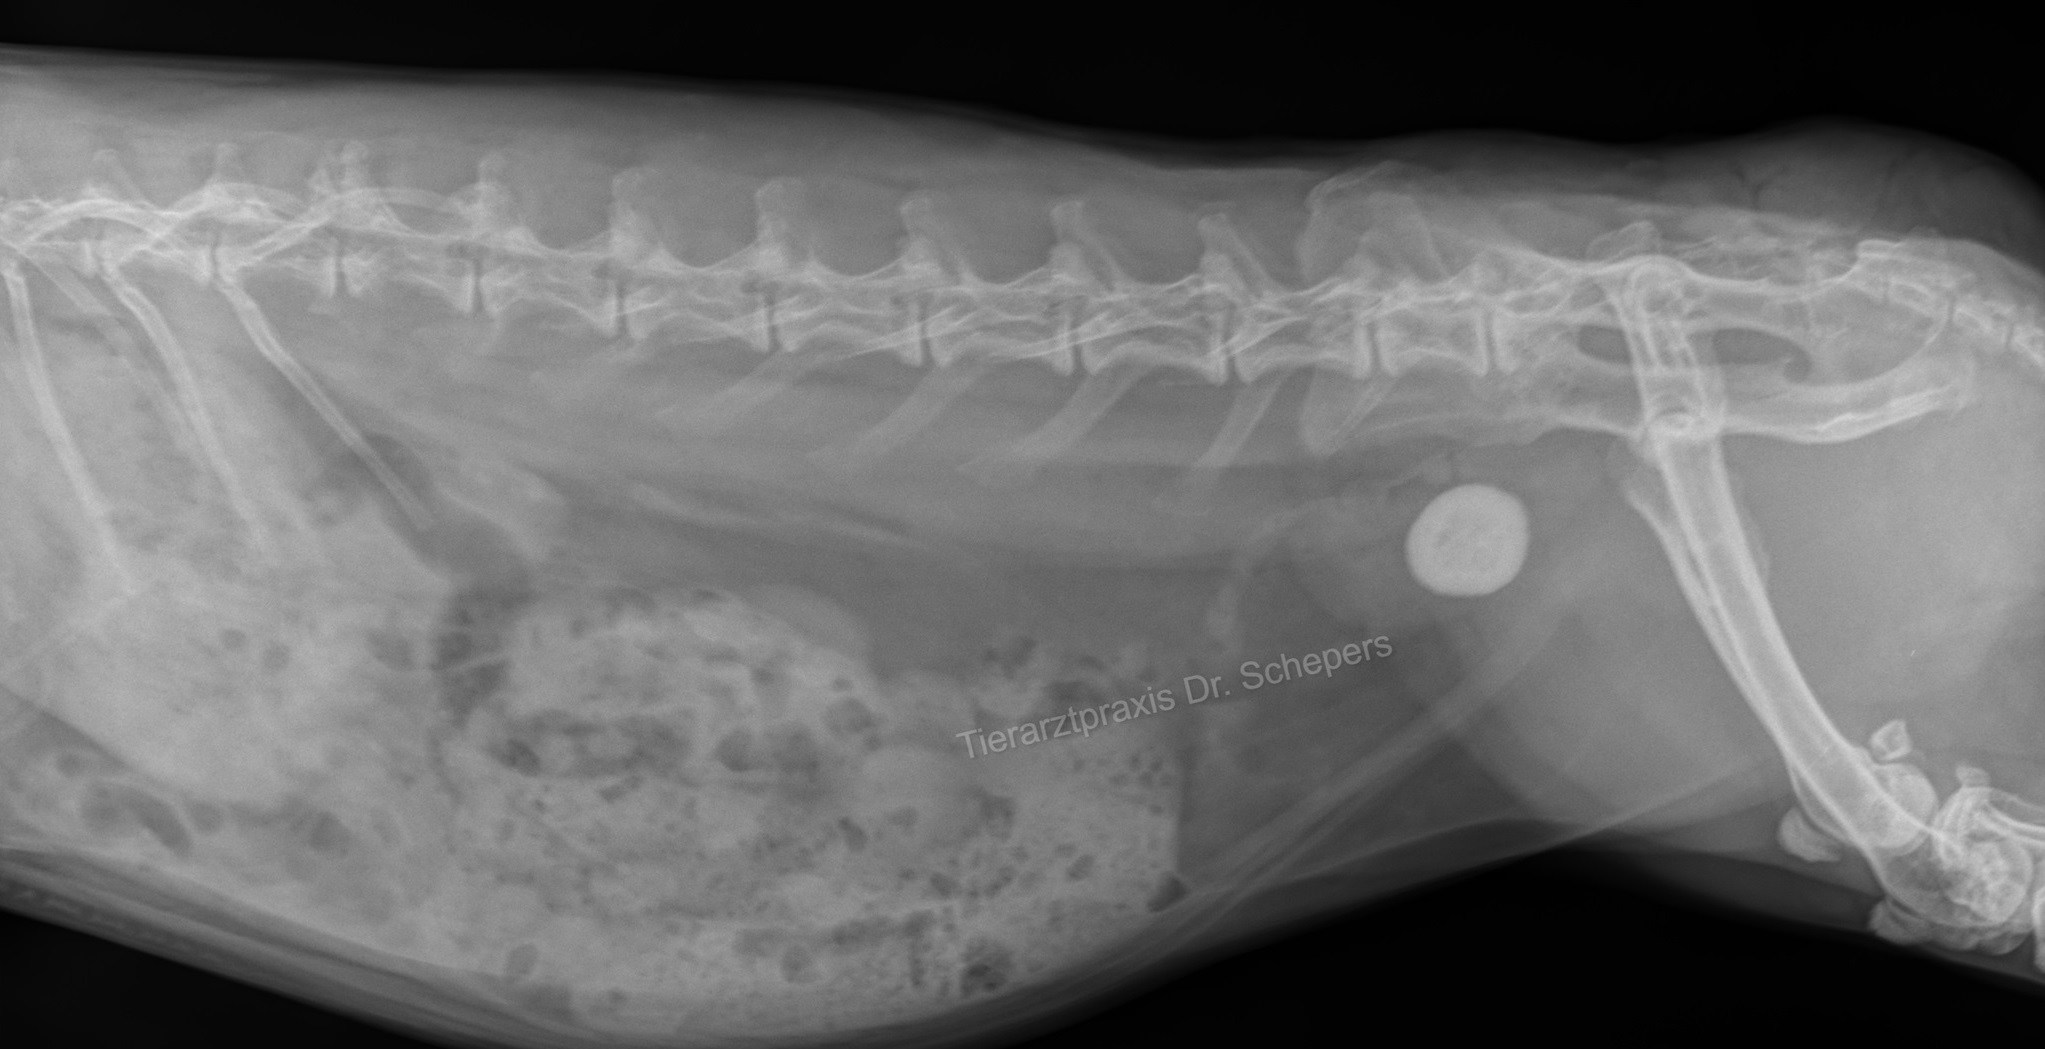

Röntgen: Auf Röntgenbildern sind Kalziumablagerungen als schneeweiße "Wolken" und Steine als solide weiße "Kreise" deutlich erkennbar. Auch Kalziumablagerungen in der Aorta und im Knochengewebe sind deutlich erkennbar. Im Gegensatz zum Ultraschall sind hier außerdem auch Steine sichtbar, die bereits in die Harnröhre gewandert sind. Um die Lokalisation zu bestimmen, sind zwei Aufnahmen aus unterschiedlichen Ebenen notwendig.

Da im Falle einer Blasenkalzinose häufig auch der übrige Harntrakt betroffen ist, sollte unbedingt ein Ganzkörperröntgen angefertigt und beim Ultraschall auch die Nieren mit kontrolliert werden.